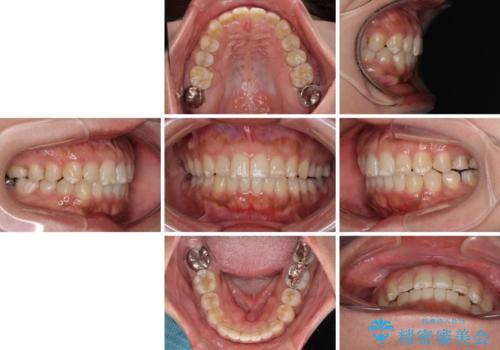

- 上下前歯の叢生を気にして来院された患者様です。

軽度な叢生であり、安価で短期間の治療を規模されていたため、インビザライン・モデレートを用いて矯正治療を行うこととしました。

- 8ヶ月